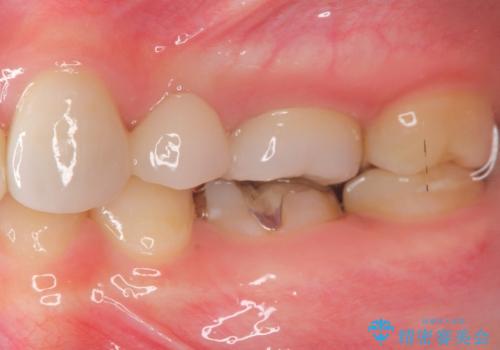

また奥歯にまたがるブリッジも金属のもので、適合もよくありませんでした。

オールセラミックによるやりかえを行いました。